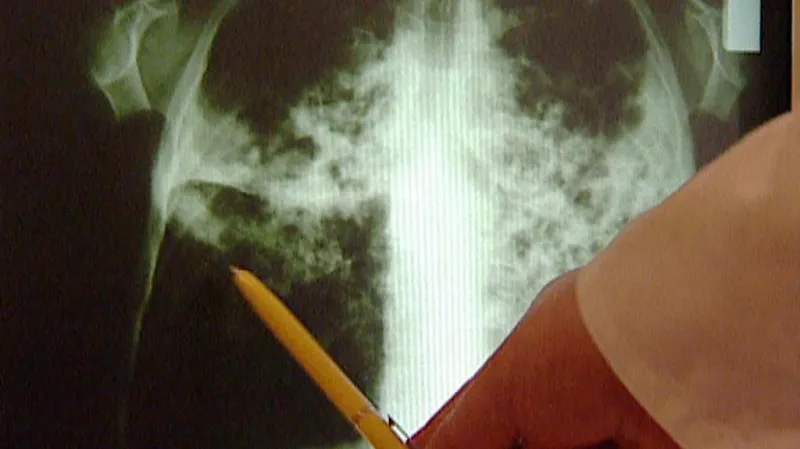

Tato nemoc sice nejčastěji postihuje dýchací cesty, ale napadá i mízní uzliny, klouby, kosti, močopohlavní trakt, kůži či mozkové pleny.

Vysoce nakažlivé onemocnění způsobují mykobakterie a jeho léčba je stále komplikovaná kvůli antibiotické rezistenci. Očkování je možné jen vakcínou BCG, která je určena především pro rizikové skupiny. Problematická u BCG je její účinnost, která se v závislosti na studiích pohybuje kolem 80 procent.